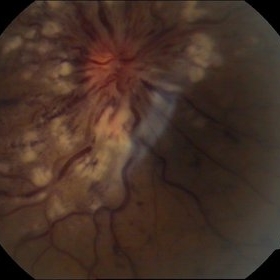

Optic Nerve Head Avulsion

Sep 15 2014 by Mehul A Shah

A 30-year-old male presented with loss of vision following blunt trauma.

Photographer: Drashti Netralaya,Dahod

Imaging device: Zeiss ff450

Condition/keywords: optic nerve head avulsion